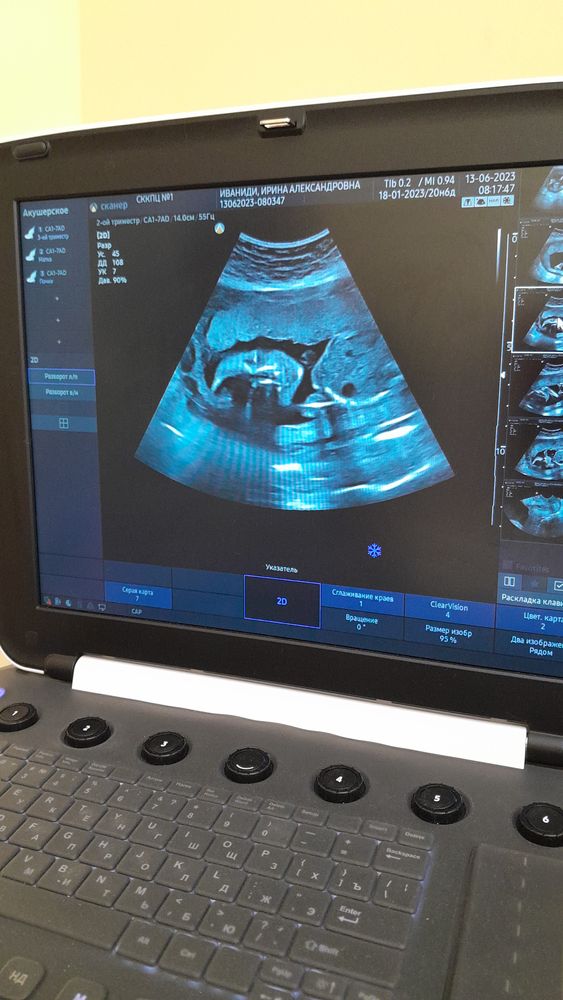

Ходили с мужем на узи, внепланово, в 18 нед и 6 дней. Малышка была 233 грамма, всё было в норме. Положение поперечное, размеры на 18 нед и 1 день(но врач уверила, что волноваться не о чем, всё замечательно).

В перинатальном центре тоже отправили на узи, на скрининг в 20 недель. Там намерили уже 350 грамм вес😍 так что, растём и радуем маму 😊 шейка на обоих узи длинная, закрытая. К 21 неделе закрыла обходной лист, слава богу! Так что теперь хожу только к гинекологу на приёмы.